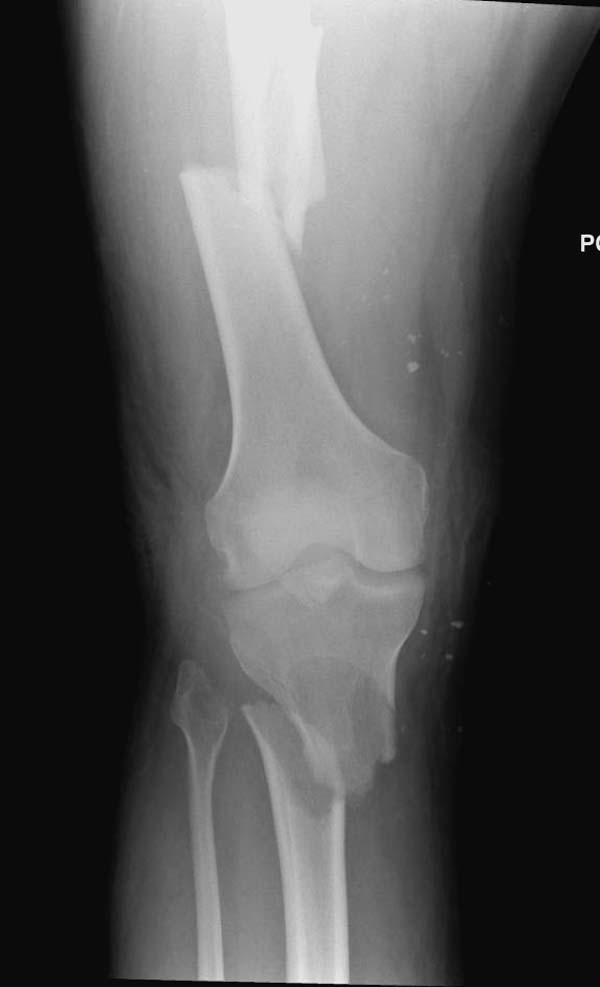

Здесь, кроме перелома верхней трети голени, имеется вовлечение сустава, и, чтобы не пропустить смещение суставной поверхности, надо делать КТ. Срезы КТ покажут о необходимости субхондральной фиксации, которая проводится 3.5 мм параллельными шурупами (Raft technique). Не имеет значения, как проводить: отдельно субхондрально или через верхний ряд пластины. Главная задача фиксации удержать суставную поверхность от коллапса в вальгус или варус.

Здесь случай, так называемого floating knee перелома выше и ниже коленного сустава.